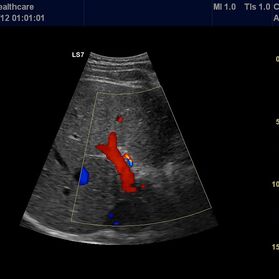

Die Ultraschall-Untersuchung ist mit Recht eine der wichtigsten und häufigsten Untersuchungsmethoden. Der Ultraschall ist ein bildgebendes Verfahren. Er erlaubt, von außen in den menschlichen Körper hinein zu sehen. So können die inneren Organe enorm detailreich und aussagekräftig untersucht werden. Vor allem die Weichteile wie Leber, Bauchspeicheldrüse, Galle, Niere oder Milz, die beim Röntgen nur schlecht zu sehen sind, können ausgezeichnet dargestellt werden.

Die Ultraschalluntersuchung ist ein sehr schnelles und leistungsstarkes Diagnoseverfahren. Dabei kann der Arzt Abläufe im Körper in Echtzeit sehen! Er hat keine Momentaufnahme vor sich, wie auf den Bildern des Röntgens oder der Computertomographie, sondern ein bewegtes Bild. Um zum Beispiel die Darmbeweglichkeit oder Organdurchblutung darzustellen, ein großer Vorteil. Da Sie als Patient dabei nicht in einer Röhre liegen, sondern ihr behandelnder Arzt neben Ihnen ist, kann ganz gezielt untersucht werden; dabei Beschwerdepunkte gezeigt, Befunde direkt erläutert und das weitere Vorgehen abgesprochen werden.

Für unsere Patienten ist eine Sonographie strahlenfrei, schmerzfrei und ohne Nebenwirkungen. Um möglichst gute Sicht zu haben, sollten Sie 6 Stunden vorher auf Essen und auf kohlensäurehaltige Getränke verzichten.